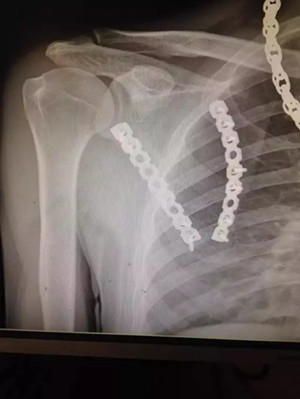

病例二

患者小陳(化名)因車禍致肩部受傷到廣安醫(yī)院就診,被診斷為“左側(cè)肩胛骨粉碎性骨折”,骨折端分離移位明顯。

術(shù)后拍片